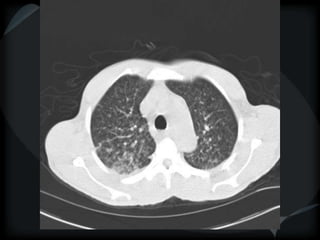

METS

random

miliary